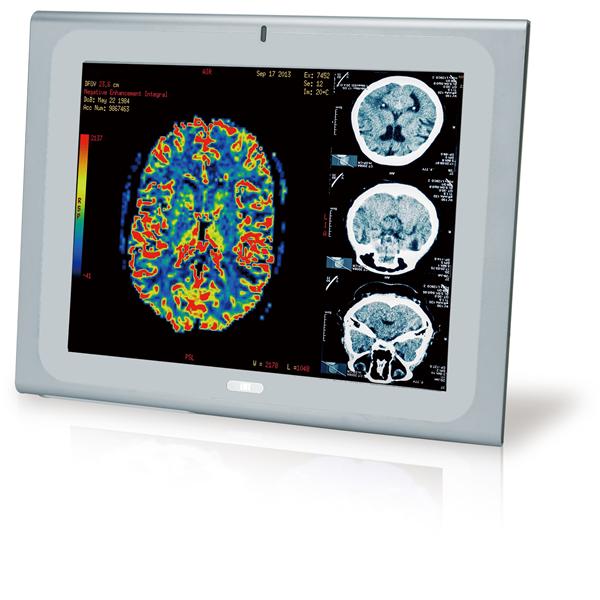

IEI Technology | Panel PCs 21.5" 250cd/m FH... |

IEI Technology | Panel PCs 17" Medical Pan... |

IEI Technology | Panel PCs 19" Medical Pan... |

IEI Technology | Panel PCs 17" Medical Pan... |

IEI Technology | Panel PCs 19" Medical Pan... |

IEI Technology | Panel PCs 17" Medical Pan... |

IEI Technology | Panel PCs 19" Medical Pan... |